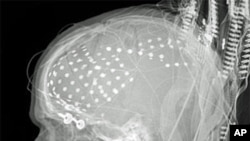

X-ray inoratidza kurapwa kwepfari.